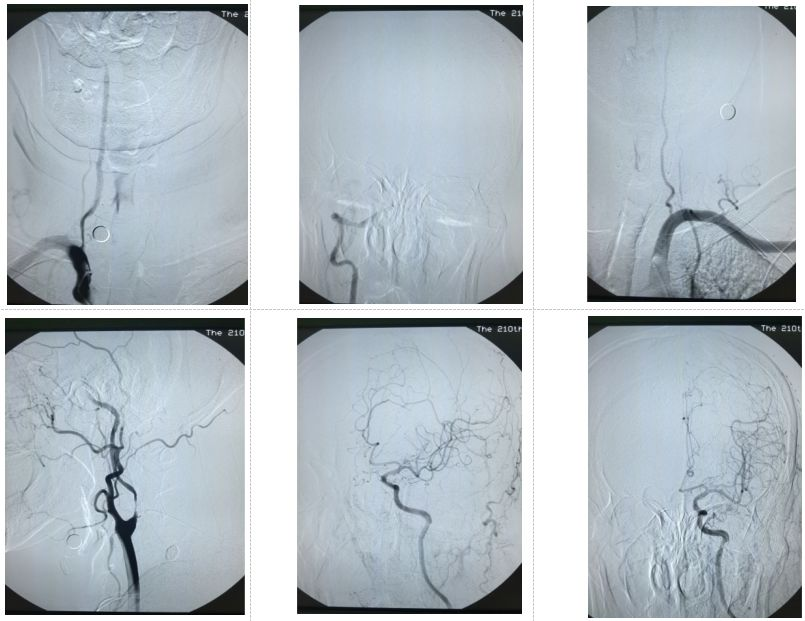

图3.DSA示右侧椎动脉起始部长段重度狭窄,颅内血流稀疏;左侧椎动脉发育不良;左侧颈内动脉起始部极重度,岩骨段及颅内大血管未见明确狭窄,颅内血流稀疏

至此,柳暗花明,拨云见日。患者的诊断最终明确:1、左侧颈内动脉起始部重度狭窄2、右侧椎动脉起始部重度狭窄。两条责任血管均重度狭窄,导致的颅内灌注偏低出现临床症状,MRA上的左侧颈内动脉岩骨段及颅内血管狭窄系因颈内动脉血流减少导致的“狭窄”假象。对于合并后循环狭窄的前循环病变,手术策略应该是先行右侧椎动脉支架成形,同期行左侧颈内动脉支架成形。